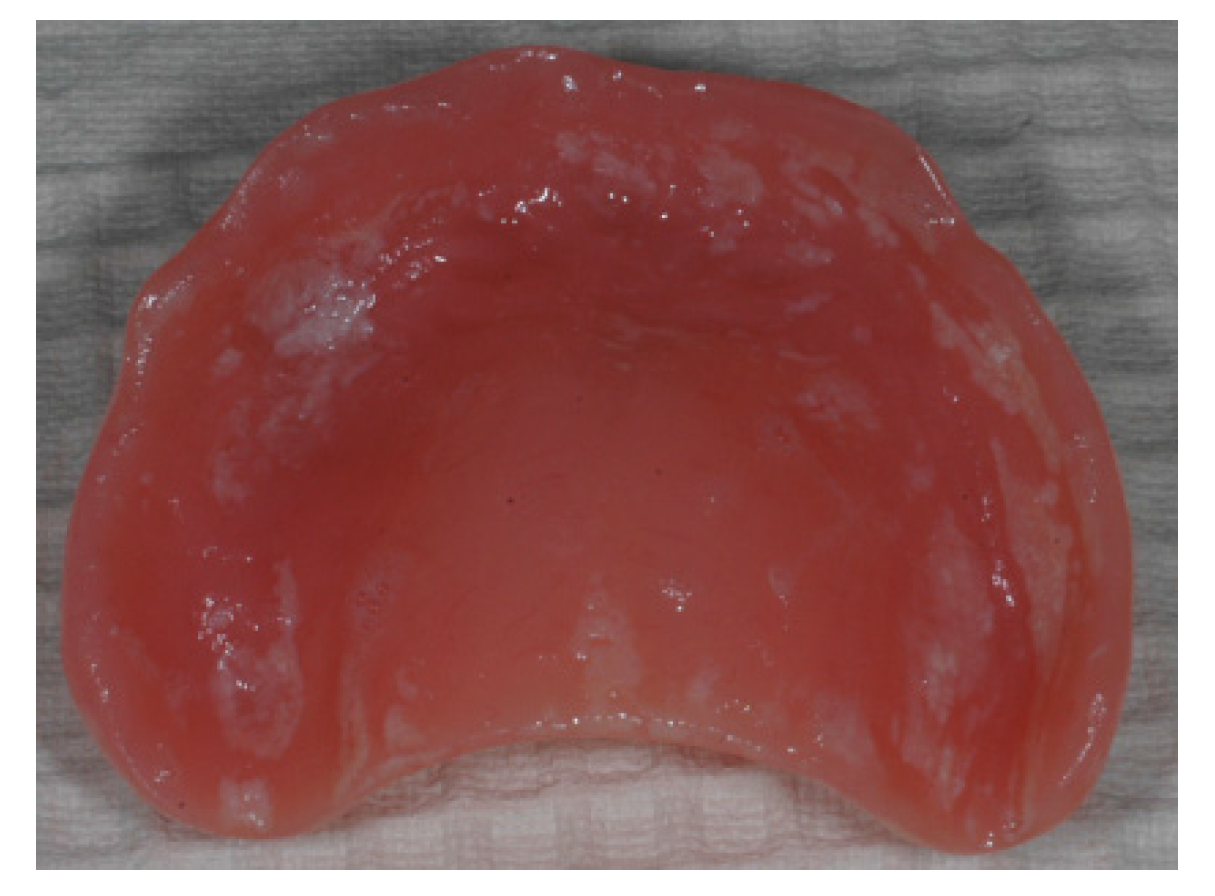

Figure 2. Patient with denture stomatitis. The infection has spread from the denture covered palate to the throat and stomach. The patient experienced no oral pain and was unaware of the situation (photo: Marit Øilo).

Oral infections can affect the hosts’ general health in many ways [8,22]. Firstly, it is unfavorable to have ongoing infections in general. Oral infections such as gingivitis can involve quite large areas, and is a constant burden for the hosts’ immune system. This is, of course, most harmful for patients with other ongoing inflammations or diseases. Secondly, oral microbes may spread to other organs within the host either via the respiratory system or through the blood stream [1,2,8,20,22,23]. This is, again, most harmful for patients with other complications, such as artificial heart valves, or transplanted organs. Elderly people with pneumonia will often have oral microbes in their lungs, which may have been aspired from the oropharynx and caused the inflammation in the lungs [8,20,23]. The direct causality between oral infections and systemic disease has been difficult to prove. It is difficult to detect whether the oral microorganisms were present prior to the disease and were the direct cause of the infection or not. It is also possible that the oral microbes entered the loci after the primary inflammation occurred due to reduced effect in the immune response system. Candida albicans can spread directly from the oral cavity to the throat and stomach (Figure 2) [24,25]. General candida infections are extremely difficult to cure due to the high risk of re-colonization. Thirdly, individuals with poor general health will normally also have poor oral health, due to malfunctioning immune system and altered chemical and physical conditions in the body, such as reduced saliva flow, iron deficiency, malnutrition, medical treatment, etc. [26,27]. Sick and elderly have reduced ability to clean their teeth properly and are therefore more exposed to development of unfavorable biofilm and subsequent general infection [28].